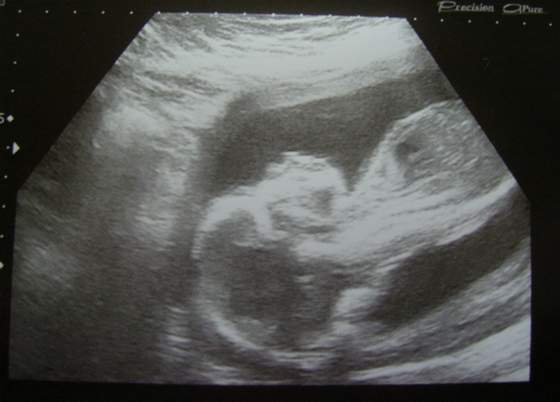

Ja już w domku... Jestem cholernie rozczarowana tym usg... :-(

Całość trwała może z kwadrans, babeczka gadała jak robot i generalnie miała w nosie nasze zdanie, polowy z tego co gadała nie zrozumiałam. Jedyny plus usg jest taki, że u Bobaska wszystko okChociaż też, badała i tylko było: "ok" to, "ok" tamto... Bez tłumaczeń, nic kompletnie :-( Dowiedziałam się, że mam łożysko na przedniej ściance macicy, do tego bardzo nisko i dostałam skierowanie na jeszcze jedno usg - w 32 tygodniu ciąży!

Od niego będzie zależało, czy urodzę normalnie, czy będzie przymusowa cesarka...

![]()

A na sam koniec jestem już w ogóle rozgoryczona, bo mimo słodkości zjedzonych przed usg po to, by dziecko się ruszało, Berbeć nie pokazał co ma między nogami!! :-( Dowiem się (albo i nie) w 32 tygodniu na tym usg... O ile będę chciała, bo tak blisko porodu to już mi obojętne i chyba wolę już mieć niespodziankę przy porodzie...

Bejbiś fajnie się ruszał podczas scanu i mamy 2 ładne zdjęcia, w tym jedno jak bobas puszcza "bąbelki". ZDROWE DZIECKO i ładne zdjęcia to jedyne, co mnie zadowoliło po tym usg, poza tym - kompletnie nic więcej...![]()

Nawet nie wiem, jak długie jest dziecko, ile waży... Nic kompletnie...

Zobacz załącznik 376681Zobacz załącznik 376682